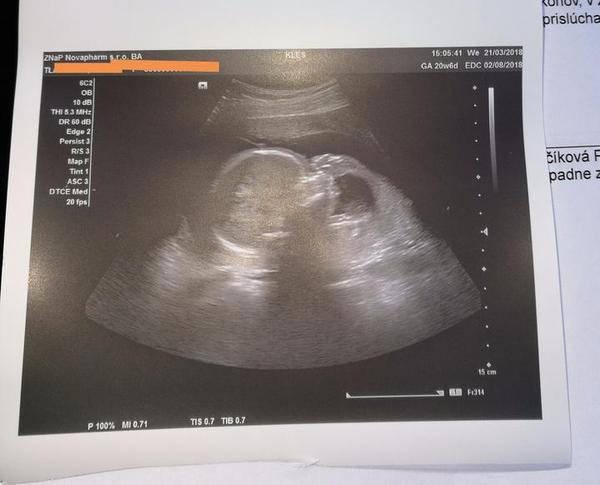

@luta13 ahooooj dakujemmm.... Ja bola u lekarky koli prechladnutiu tak hned ma pozrela.. Sliznica vysoko, 4.3mm fliacik je Tam, hcg 150-zodpoveda 4tt... Za dva tyzdne idem na kontrolu tak uvidime.... Bojujem s cigaretami snazim Sa znizovat... 5denne ze smiem snaziiiiiiim..... Tak hadam to tento x potiahneme do uspesneho Konca